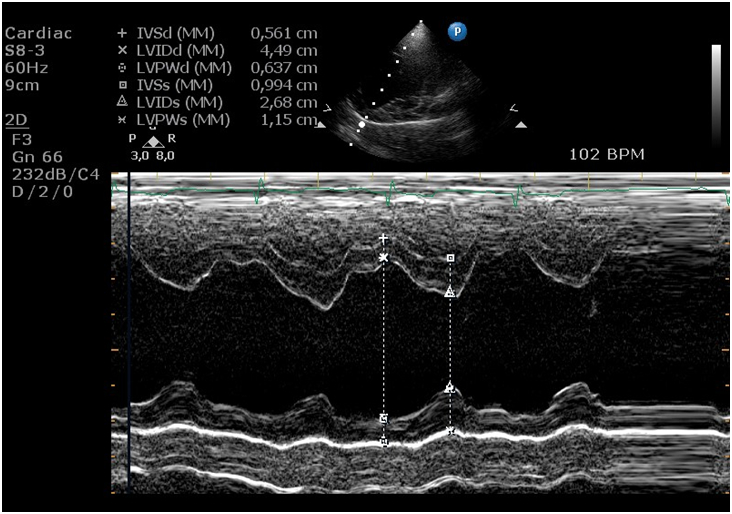

Mitte der 90er Jahre wurde mittels besserer Herzultraschallgeräte immer mehr bekannt über den DCM- Krankheitsprozess. Im Prinzip erweitert sich langsam aber sicher die linke Herzwand und im nach hinein auch das Septum zwischen linker und rechter Herzkammer. Somit tritt Leckage der linken Herzklappe auf und erweitert dadurch auch den linken Vorhof. Dies führt zu einer Störung der elektrischen Übertragung in der Vorhofwand, wodurch Herzrhythmusstörungen auftreten können.

Weil nur mittels einer Herzultraschalluntersuchung DCM definitiv diagnostiziert werden kann, sollte auch diese Untersuchung Pflicht sein für die Zucht.